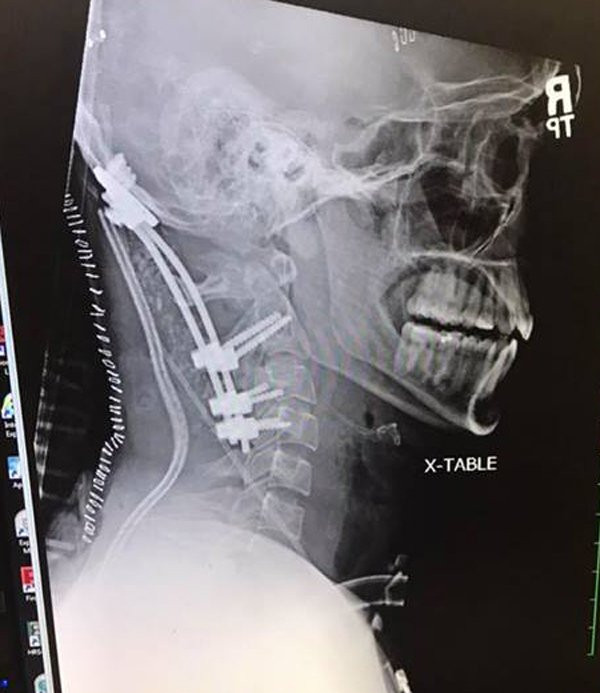

Khi xe cứu thương đến, Brock lập tức được đưa đến bệnh viện Memorial ở South Bend, Indiana. Tại đây các bác sĩ phát hiện ra rằng vùng cổ và đầu của Brock đã bị đứt lìa, cụ thể là hộp sọ của anh đã bị tách hoàn toàn khỏi cột sống. Nếu không có người bạn giữ anh nằm yên và không di chuyển thì anh có thể đã mất mạng.

| Xương sọ của anh đã rời khỏi cột sống |

Brock đã trải qua rất nhiều cuộc phẫu thuật, sức khỏe dần dần hồi phục. Cuối cùng, anh được ra viện vào tháng 2 năm 2018. Hiện tại anh đang trải qua liệu pháp vật lý trị liệu tại Bệnh viện Memorial để điều trị các vấn đề y khoa liên quan đến chấn thương cổ.